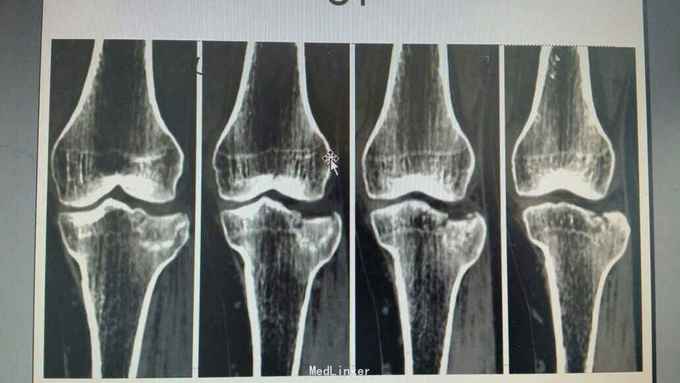

胫骨外侧平台骨折塌陷2型,关节镜下辅助骨折复位内固定术

微创手术适用于2型骨折,创伤小,恢复快,术后膝关节并发症小,患者痛苦明显减轻